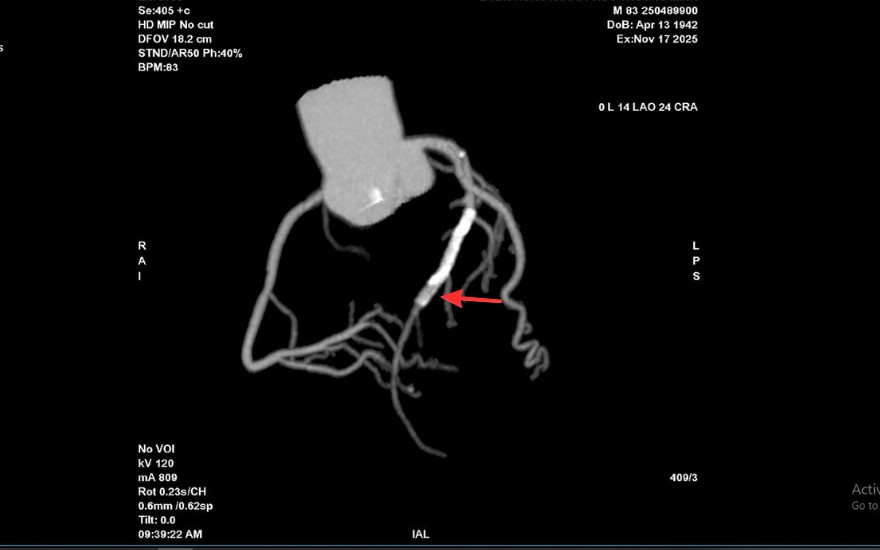

Tại Bệnh viện Đa khoa Hồng Ngọc, kết quả chụp CT 2560 lát cắt cho thấy tình trạng nghiêm trọng hơn nhiều so với biểu hiện ban đầu: mảng xơ vữa lan rộng gây hẹp nặng đoạn đầu động mạch liên thất trước và gần như làm tắc hoàn toàn lòng stent cũ. Đây là dấu hiệu cho thấy nguy cơ biến chứng tim mạch cấp tính có thể xảy ra bất cứ lúc nào nếu không được can thiệp kịp thời.

Vị trí hẹp khít trong lòng stent cũ của ông T trên hình chụp CT mạch vành 2560 lát cắt - Ảnh BVCC

Kết quả chụp mạch vành qua da trước can thiệp cho thấy mức độ tổn thương của ông T. nghiêm trọng hơn dự kiến. Lòng stent cũ tái hẹp tới 99%, trong khi đoạn mạch phía trước vị trí đặt stent cũng hẹp khoảng 90%, khiến dòng máu nuôi tim bị chậm đáng kể.